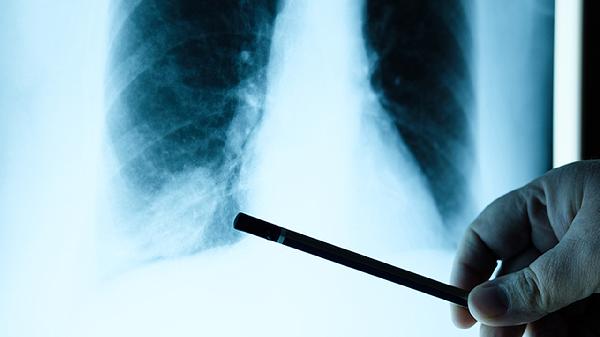

定期高分辨率CT和肺功能检查是关键,建议每6-12个月评估一次。避免妊娠、吸烟等加速病情因素,接种流感疫苗和肺炎疫苗可预防呼吸道感染。营养支持应保证足够热量摄入,防止呼吸肌消耗。